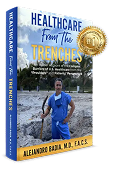

E.G. is a young man who was lending a helping hand in his father’s auto shop when he nearly gave up that hand to a freak accident. He was changing a truck tire when it suddenly exploded causing his elbow to dislocate and nearly amputate his hand. The wrist injury was so severe that it required a surgical fusion once he had been transferred to a Miami Hospital from a more remote location.

The hand surgeon on call had not accepted the transfer due to the severity of the injury, but Dr. Badia was later called and authorized the transfer so that he could perform the reconstruction. E.G.was an inspiration to the other patients in therapy undergoing months of rehabilatation so that he could regain nearly normal motion in his elbow and a functioning hand seen in the comparison photos to his opposite, normal hand